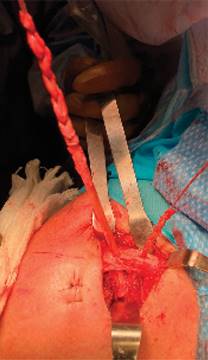

Se hace una incisión de 3 a 2 cm distal del borde lateral del acromion, por donde se pasa guía de nitinol por debajo del acromion. Se efectúa reducción manual de articulación AC, mientras un ayudante realiza fijación de injerto en los orificios de la clavícula con dos tornillos de biotenodesis 5 × 15 mm observando una adecuada fijación del injerto y restableciendo la estabilidad vertical (Figura 7). Posteriormente, el remanente de cabo distal del injerto se pasa por debajo del acromion con ayuda de la guía de nitinol en la incisión lateral y se sutura con su cabo proximal en el borde superior de la clavícula con una sutura no absorbible (Figuras 8 y 9).

Figura 7: Vista superior de la clavícula en un hombro izquierdo. Se observa la reducción de la articulación acromioclavicular y la fijación del injerto con dos tornillos bioabsorbibles. El cabo distal del injerto pasa por debajo del acromion y se fija con el mismo injerto con una sutura no absorbible cerca del orificio lateral.